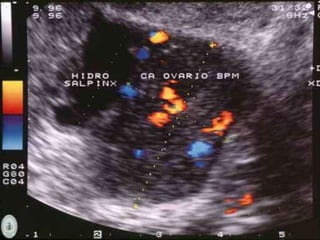

Imagenología

 Ecografía

 Tumores malignos: Multiloculados, sólidos ó ecogénicos,

mayores de 5cm, tabiques gruesos con áreas de

nodularidad.

 Flujometría doppler: Proyecciones papilares,

neovascularización.

Imagenología  Ecografía  Tumoresmalignos: Multiloculados, sólidos ó ecogénicos, mayores de 5cm, tabiques gruesos con áreas de nodularidad.  Flujometría doppler: Proyecciones papilares, neovascularización.  USG abdominal de difícil interpretación en pacientes con enfermedad avanzada o masas tumorales grandes.  Ascitis. Schorge JO, Schaffer JI, Halvorson LM, Hoffman BL, Bradshaw KD, Cunningham G. “Cáncer ovárico epitelial”. En: Schorge JO, Schaffer JI, Halvorson LM, Hoffman BL, Bradshaw KD, Cunningham G. Williams de Ginecología. México: McGraw.-Hill; 2009. Pp. 716-737.

• #25 Multiloculares e hipoecoicos. Tumores serosos y mucinosos.